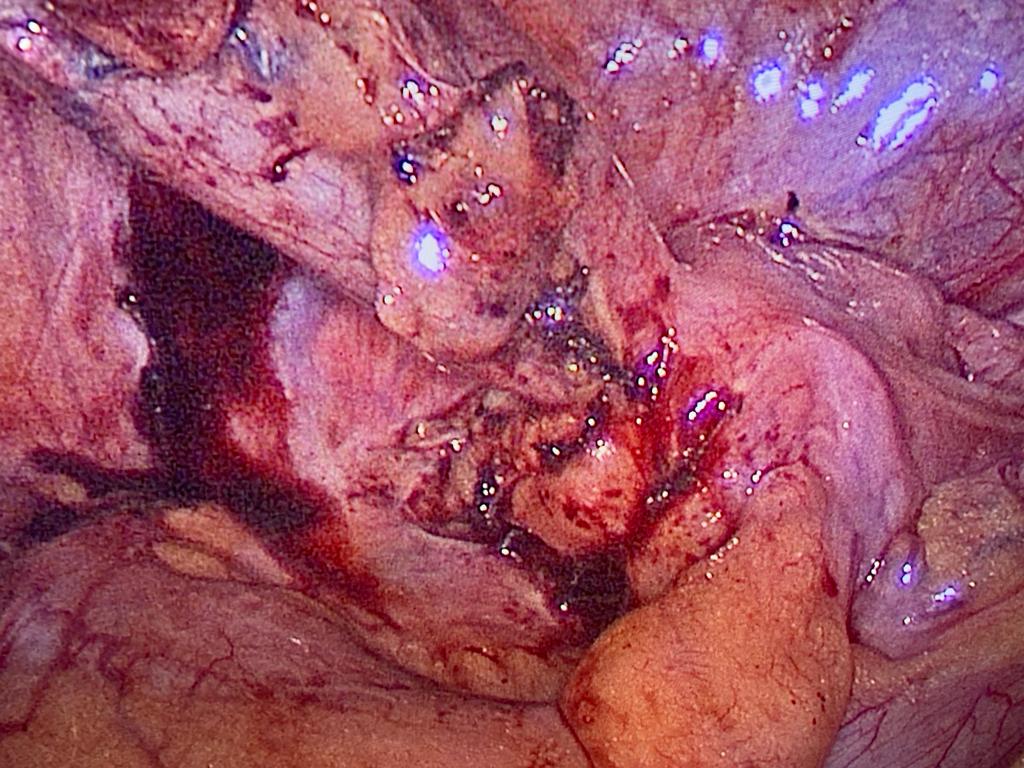

Difficult retrocecal appendix completely done laparoscopically

Difficult cases of appendicitis done completely laparoscopically